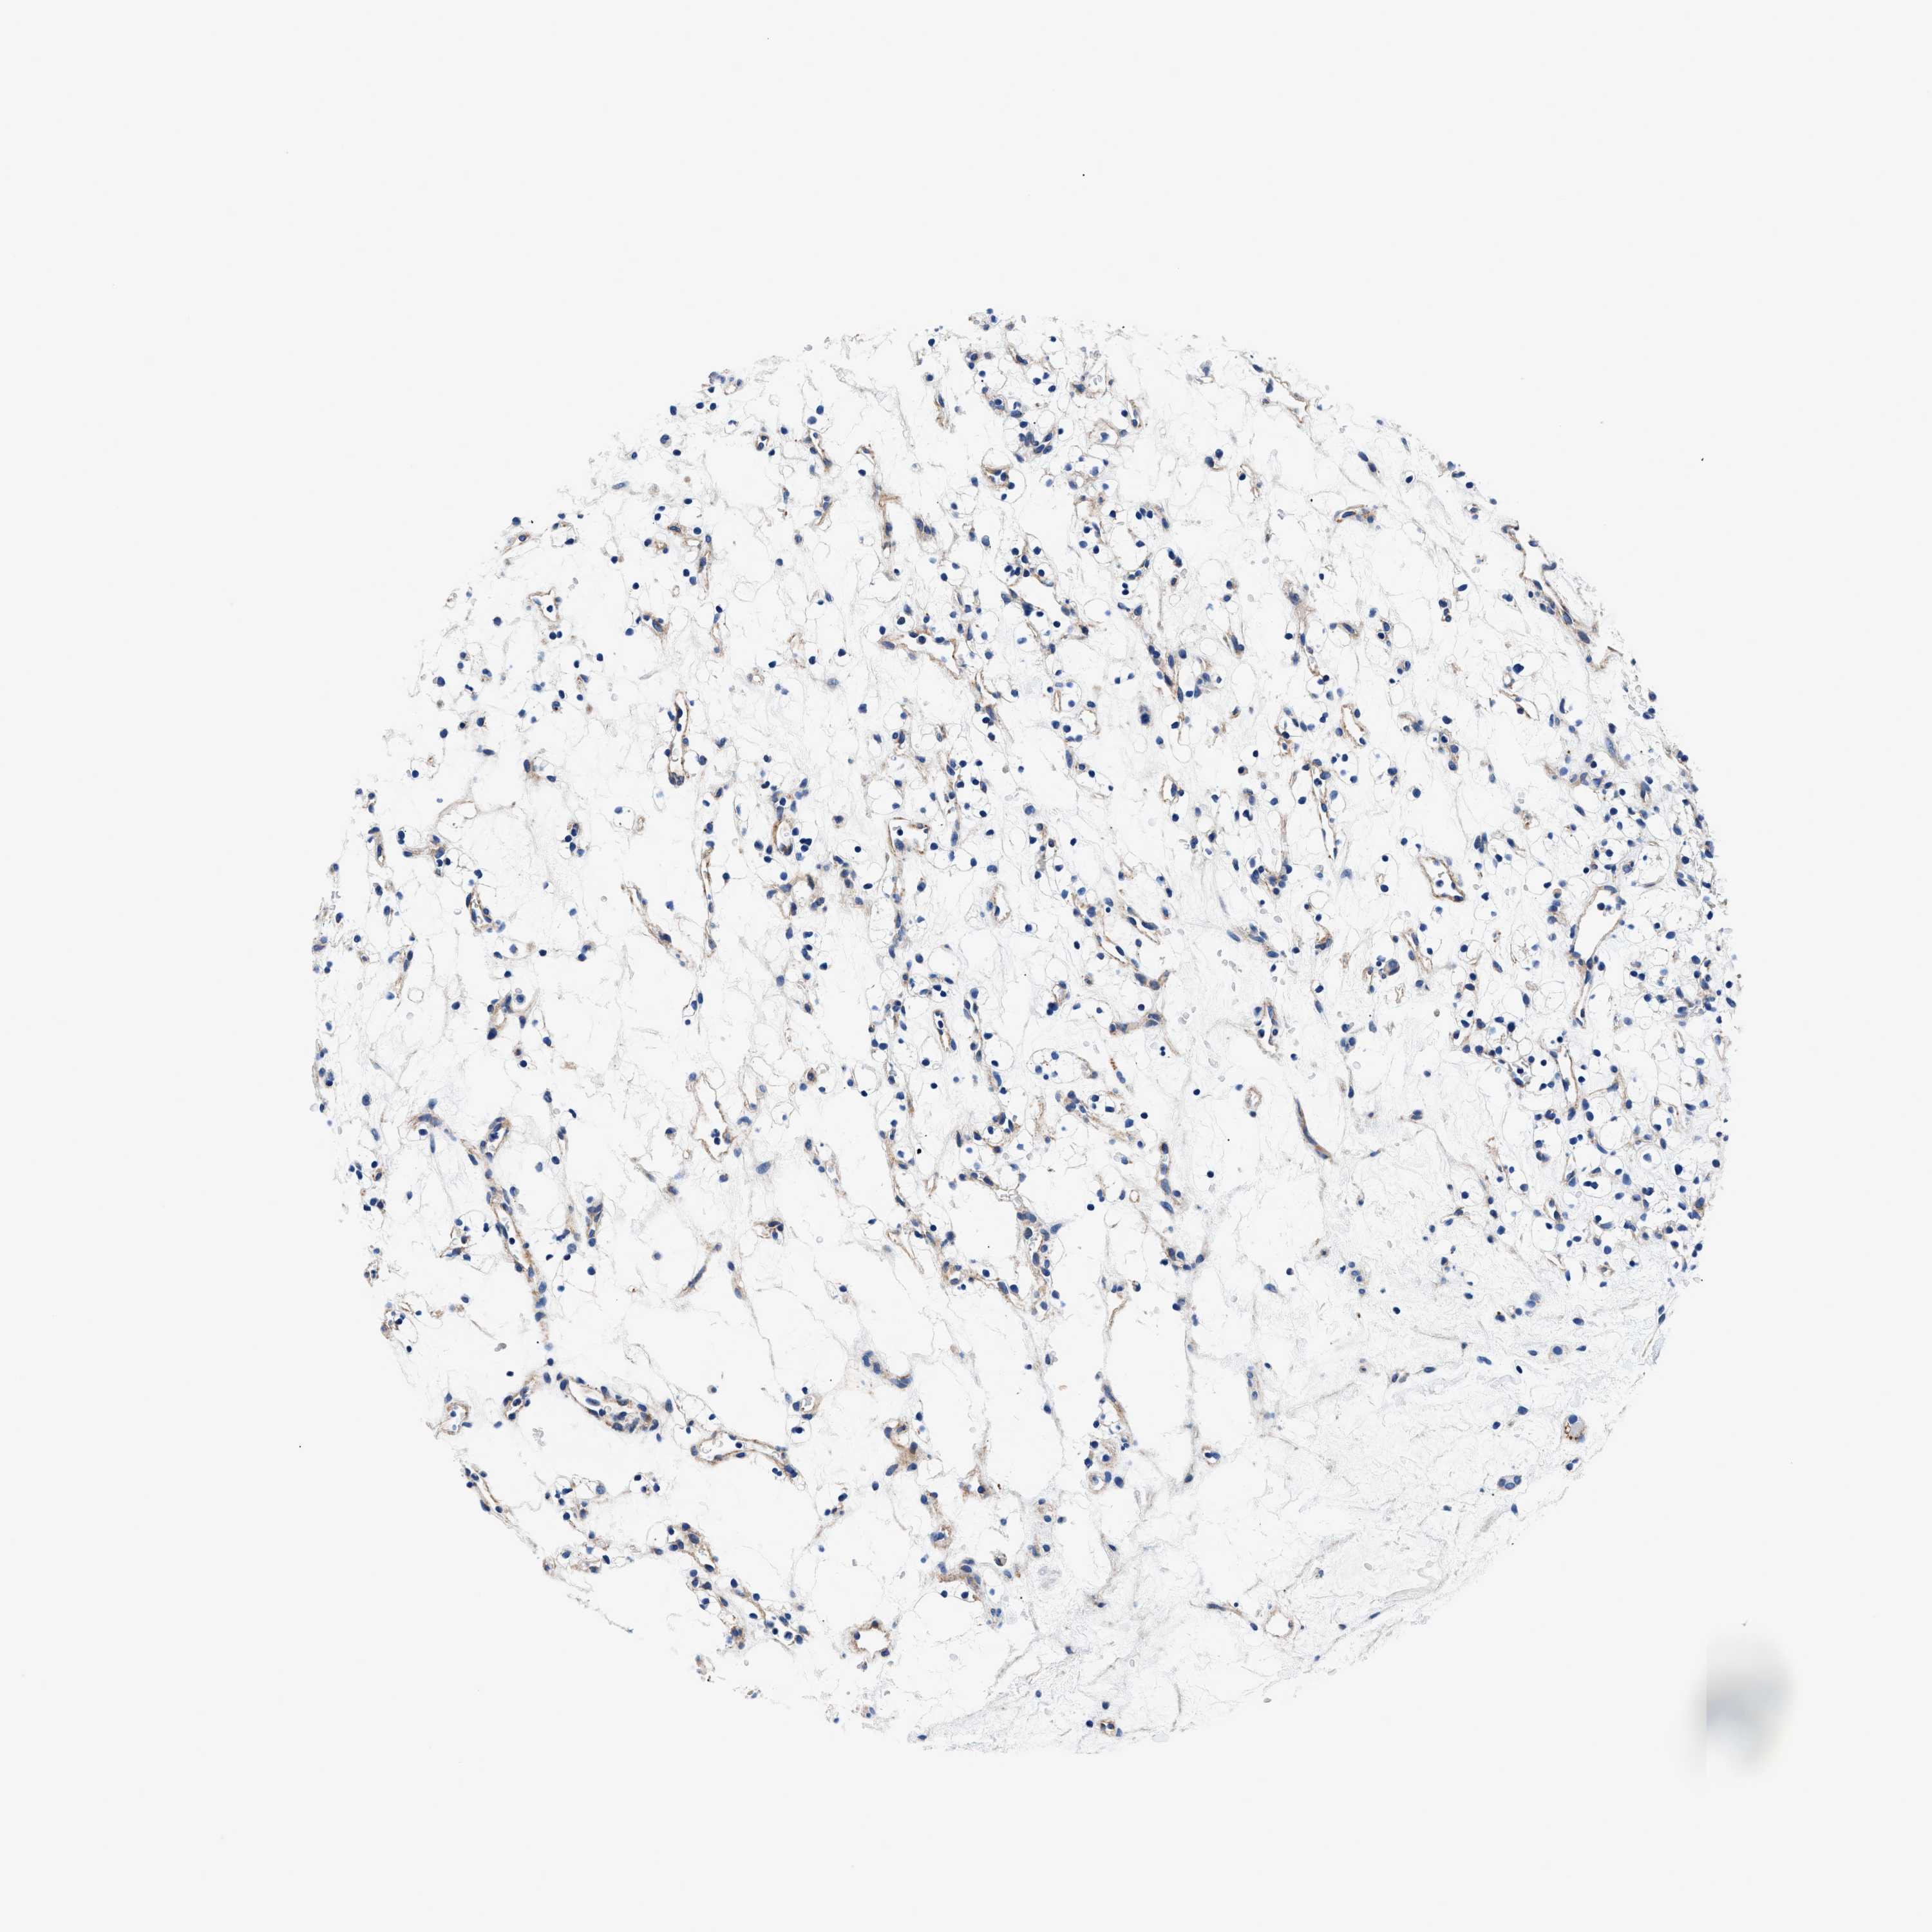

KIDNEY RENAL CLEAR CELL CARCINOMA (VALIDATION) - Interactive survival scatter ploti

The Survival Scatter plot shows the clinical status (i.e. dead or alive) for all individuals in the patient cohort, based on the same data that underlies the corresponding Kaplan-Meier plots. Patients that are alive at last time for follow-up are shown in blue and patients who have died during the study are shown in red.

The x-axis shows the expression levels (FPKM) of the investigated gene in the tumor tissue at the time of diagnosis. The y-axis shows the follow-up time after diagnosis (years). Both axes are complimented with kernel density curves demonstrating the data density over the axes. The top density plot shows the expression levels (FPKM) distribution among dead (red) and alive patients (blue). The right density plot shows the data density of the survived years of dead patients with high and low expression levels respectively, stratified using the cutoff indicated by the vertical dashed line through the Survival Scatter plot. This cutoff is automatically defined based on the FPKM cutoff that minimizes the p-score. The cutoff can be changed by dragging the vertical line or by entering a cutoff value in the square labeled "Current cut-off".

Under the Survival Scatter plot the p-score landscape (black curve; left axis) is shown together with dead median separation (red curve; right axis). Dead median separation is the difference in median mRNA expression between patients who have died with high and low expression, respectively. It is calculated as follows: median FPKM expression of dead patients with high expression - median FPKM expression of dead patients with low expression. This is intended to aid the user in visually exploring custom cutoffs and the associated p-scores and dead median separation.

Individual patient data is displayed and can be filtered by clicking on one or more of the category buttons on the top of the page. Categories describing expression level and patient information include: high, low, alive, dead, female, male and tumor stages. The scale of the x-axis can be toggled between linear and log-scale by clicking on the "x log" button. Mouse-over function shows TCGA ID, patient information and mRNA expression (FPKM) for each patient.

& Survival analysisi

Kaplan-Meier plots summarize results from analysis of correlation between mRNA expression level and patient survival. Patients were divided based on level of expression into one of the two groups "low" (under cut off) or "high" (over cut off). X-axis shows time for survival (years) and y-axis shows the probability of survival, where 1.0 corresponds to 100 percent.

DAG1 is not prognostic in Kidney Renal Clear Cell Carcinoma (validation)

Best expression cut offi

Based on the FPKM value of each gene, patients were classified into two groups and association between prognosis (survival) and gene expression (FPKM) was examined. The best expression cut-off refers the FPKM value that yields maximal difference with regard to survival between the two groups at the lowest log-rank P-value. Best expression cut-off was selected based on survival analysis .

When clicking on this number, the vertical dashed line indicating cut-off, the interactive survival plot, and the Kaplan-Meier curve will be adjusted to show results based on the best expression cut-off.

: 23.41

P scorei

Log-rank P value for Kaplan-Meier plot showing results from analysis of correlation between mRNA expression level and patient survival.

N/A

TCGA RNA samplesi

RNA-seq data is reported as average FPKM (number Fragments Per Kilobase of exon per Million reads), generated by the The Cancer Genome Atlas (TCGA) .

Normal distribution across the dataset is visualized with box plots, shown as median and 25th and 75th percentiles. Points are displayed as outliers if they are above or below 1.5 times the interquartile range. FPKM values of the individual samples are presented next to the box plot.

Average pTPM 26.4

Number of samples 100